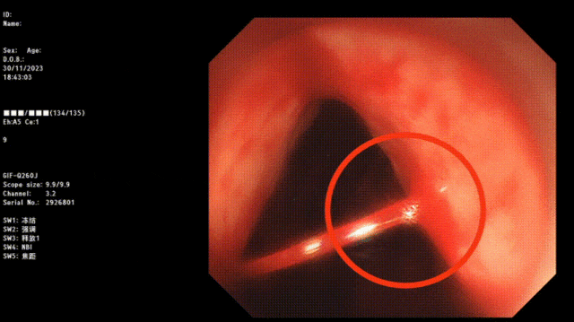

Part.04病因診斷有哪些方式?

1. 內(nèi)鏡檢查:包括胃鏡、結腸鏡等內(nèi)鏡檢查技術,可以直接觀察到消化道黏膜的情況,幫助醫(yī)生確定出血的原因。

image.png

止血成功